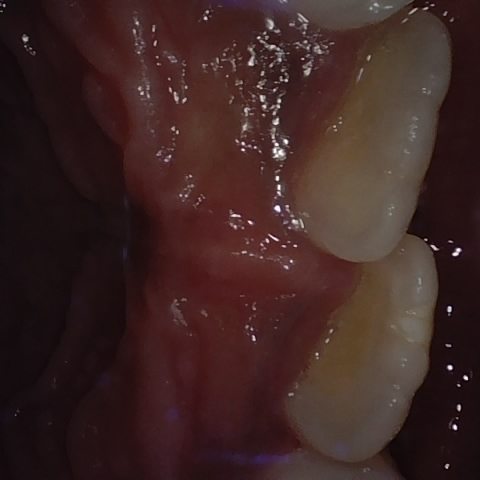

Image 208 / 1103

NHD39174

Annotated as "Good"

Original Image Rendering Image